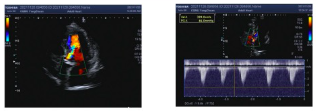

超声评估:

主动脉瓣上峰值流速:3.4m/s,术前跨瓣压差:45.7mmHg,EF值52%,左室前后径48mm,室间隔厚13mm。

心脏彩超提示:左房增大、左室壁增厚、升主动脉增宽、主动脉瓣钙化、主动脉瓣中度狭窄伴重度关闭不全、二尖瓣轻度关闭不全。